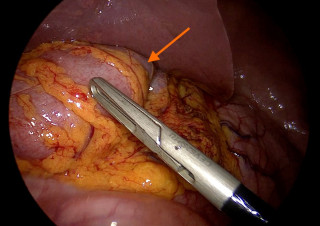

Case presentation

A 55-year-old overweight man presented with one week of right-sided abdominal pain with recent worsening despite outpatient medical therapy. He was hemodynamically stable but had right upper quadrant tenderness and localized guarding. Laboratory testing showed elevated C-reactive protein with a normal leukocyte count and normal liver biochemistry. CT demonstrated inflammatory fat stranding of the right greater omentum with a hyperdense rim, consistent with right-sided omental infarction (Figure 1). Because pain persisted despite conservative management, diagnostic laparoscopy was performed and confirmed ischemic omentum with hemorrhagic peritoneal fluid (Figure 2), and a normal gallbladder and appendix. Laparoscopic omentectomy was completed without complications. Histopathology confirmed omental infarction (Figure 3). The patient was discharged on postoperative day 1 and remained asymptomatic at 6-week follow-up.